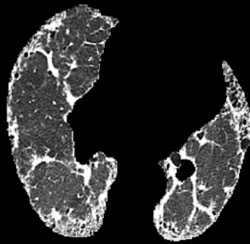

In the field of medical imaging, particularly in tasks related to early disease detection and prognosis, understanding the reasoning behind AI model predictions is imperative for assessing their reliability. Conventional explanation methods encounter challenges in identifying decisive features in medical image classifications, especially when discriminative features are subtle or not immediately evident. To address this limitation, we propose an agent model capable of generating counterfactual images that prompt different decisions when plugged into a black box model. By employing this agent model, we can uncover influential image patterns that impact the black model's final predictions. Through our methodology, we efficiently identify features that influence decisions of the deep black box. We validated our approach in the rigorous domain of medical prognosis tasks, showcasing its efficacy and potential to enhance the reliability of deep learning models in medical image classification compared to existing interpretation methods. The code will be publicly available at https://github.com/ayanglab/DiffExplainer.